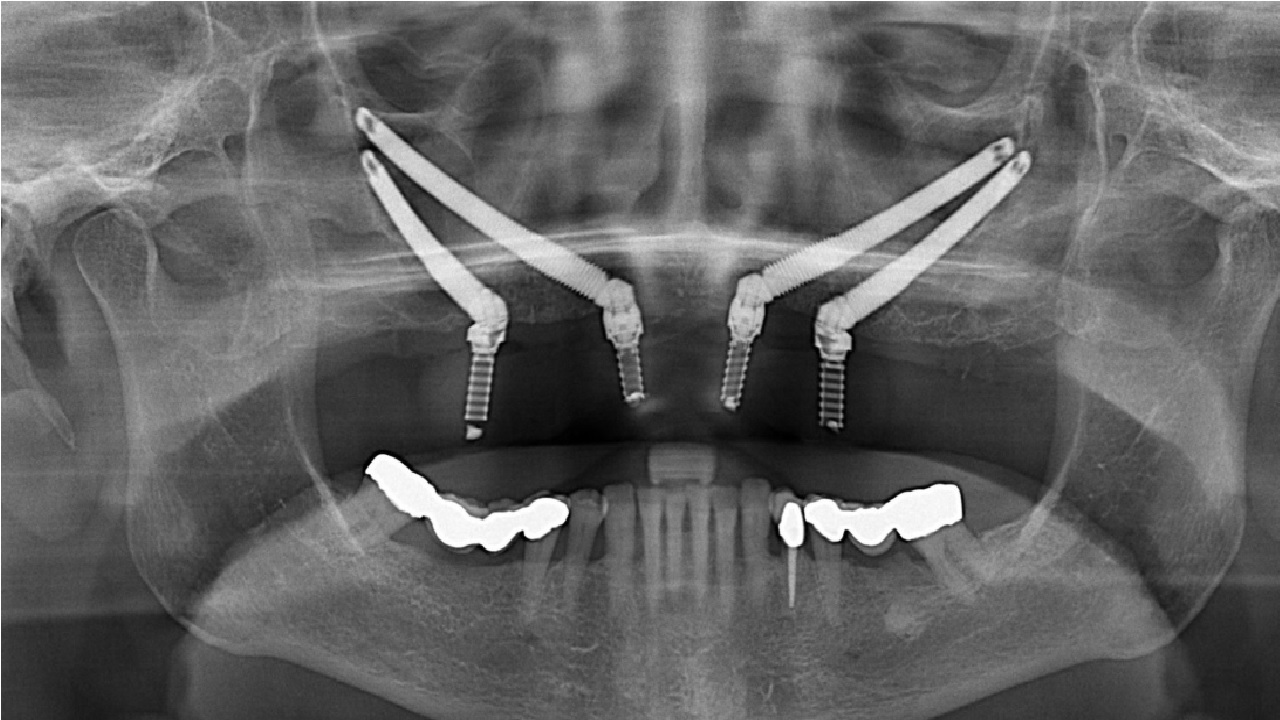

Comprehensive Digital Planning & Guided Surgery

At the MaxFax Zygoma Center in Istanbul, every procedure begins with CBCT-based 3D analysis, prosthetics-driven digital planning, and navigation-guided implant placement. This workflow minimizes risks, enhances accuracy, and allows immediate loading of fixed restorations when clinically appropriate.